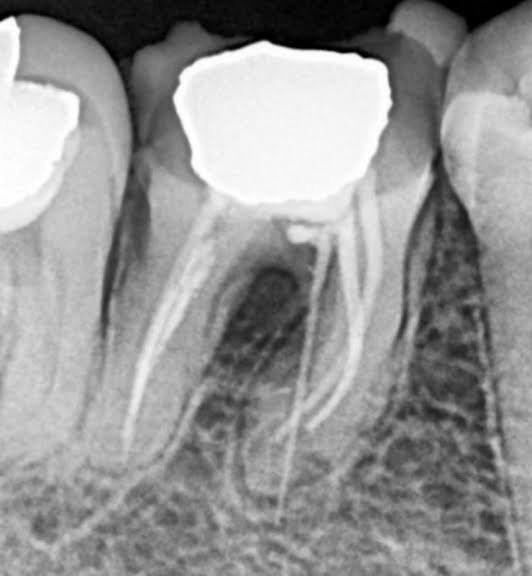

2. What Condition can be seen in this X ray regarding the tooth # 4.4.?